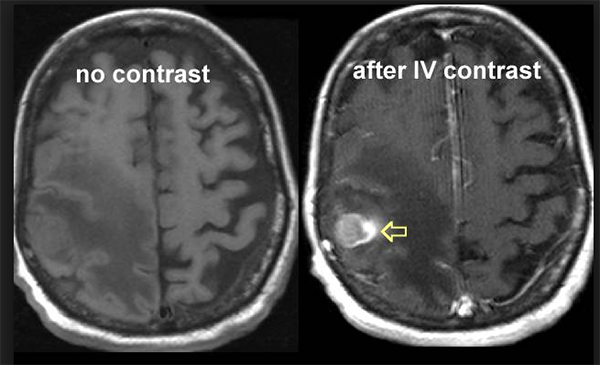

Gadolinium Contrast

https://www.radiologymasterclass.co.uk/images/mri/mri_gad.jpg?mtime=20210304211353&focal=none